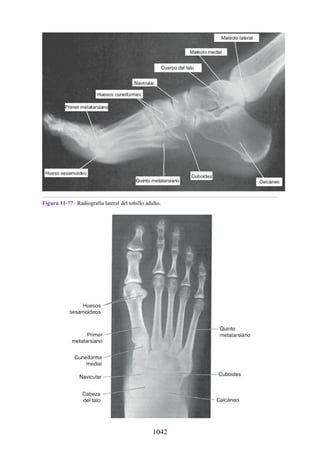

Notas clínicas

Lesiones ligamentosas